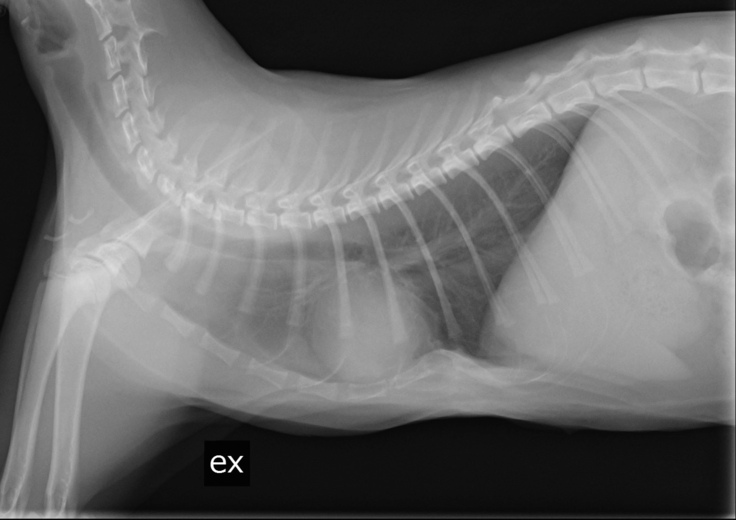

これは胸骨の位置を矯正する為のプレートを入れた際の写真です。